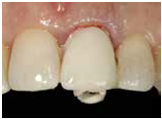

並於100/10/25將中間兩顆植體做二階接出

由於前後植體的高低差距太大,決定將中間兩顆高度較為一致的植體假牙做連結,但前後兩顆做單顆假牙的設計。

100/11/21 補綴完成

目前植體周圍的組織都很理想健康並追蹤中。